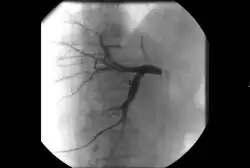

• Ангиография : визуализация кровеносных сосудов для выявления аномалий с использованием различных контрастных веществ, включая йодированный контраст, вещества на основе гадолиния газ CO2 .[3]

ангиография артериита Такаясу